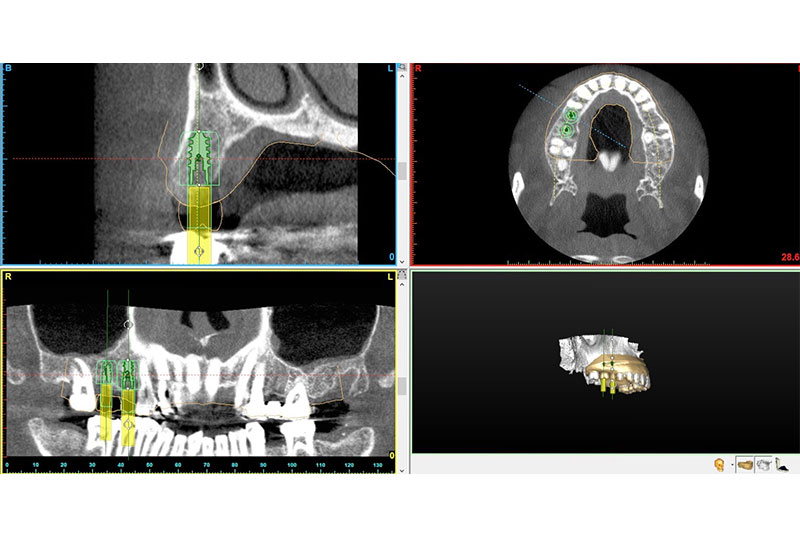

CT撮影を使用した精度の高いシュミレーション

当院では、インプラント埋入の前に必ずCT撮影を実施しています。

CT画像によって、お口の中を立体的(3D)に確認できるだけでなく、骨の厚みや密度なども詳細に把握することが可能です。

骨の厚みを確認せずにインプラントを埋入すると、骨が薄い部分では後にインプラントが脱落するなどのトラブルにつながる恐れがあります。そのようなリスクを未然に防ぐため、当院ではCT撮影による精密な診断と高精度なシミュレーションを行っております。